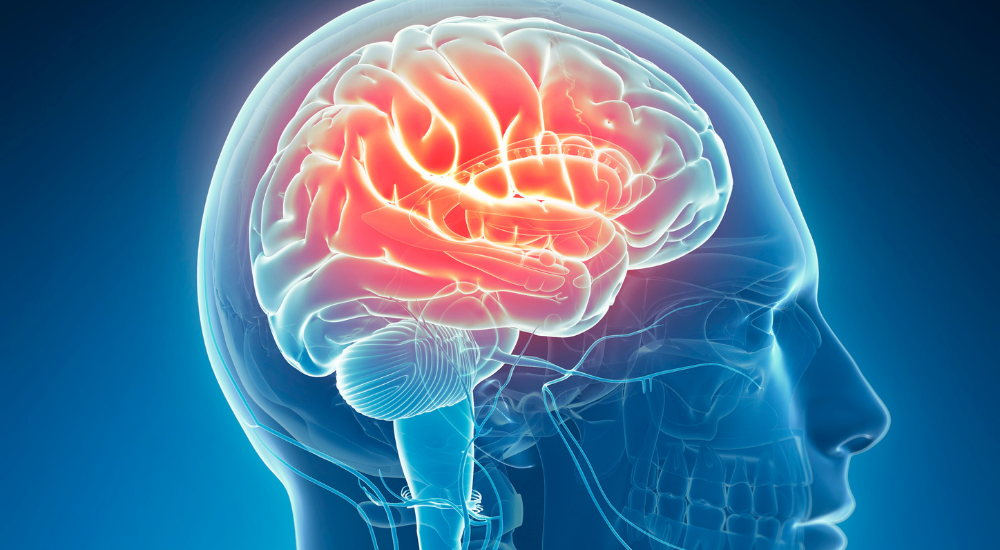

しかし、慢性的なストレスや不良姿勢による持続的な筋緊張は、筋肉やその周りの筋膜に豊富に存在するセンサーを通じて、脳へ継続的に信号を送ります。

これらの信号は自律神経系に影響を与え、特に交感神経を過剰に刺激する可能性があります。

身体が常に「危険信号」を受け取っているような状態になり、交感神経が優位な状態が続くと、心身はリラックスできず、疲労感が蓄積しやすくなります。

また、首周りや背骨の近く、内臓周囲など、自律神経に関わる重要な神経が通る場所の筋肉や筋膜が硬くなると、神経の働きが妨げられたり、不適切な信号が送られたりして、自律神経のバランスがさらに乱れることがあります。

これを「自律神経反射」と捉えることもできます。

身体の特定の部位の緊張が、反射的に自律神経の働きに影響を与え、気分の落ち込み、不安、不眠といった症状を引き起こしたり、悪化させたりするのです。